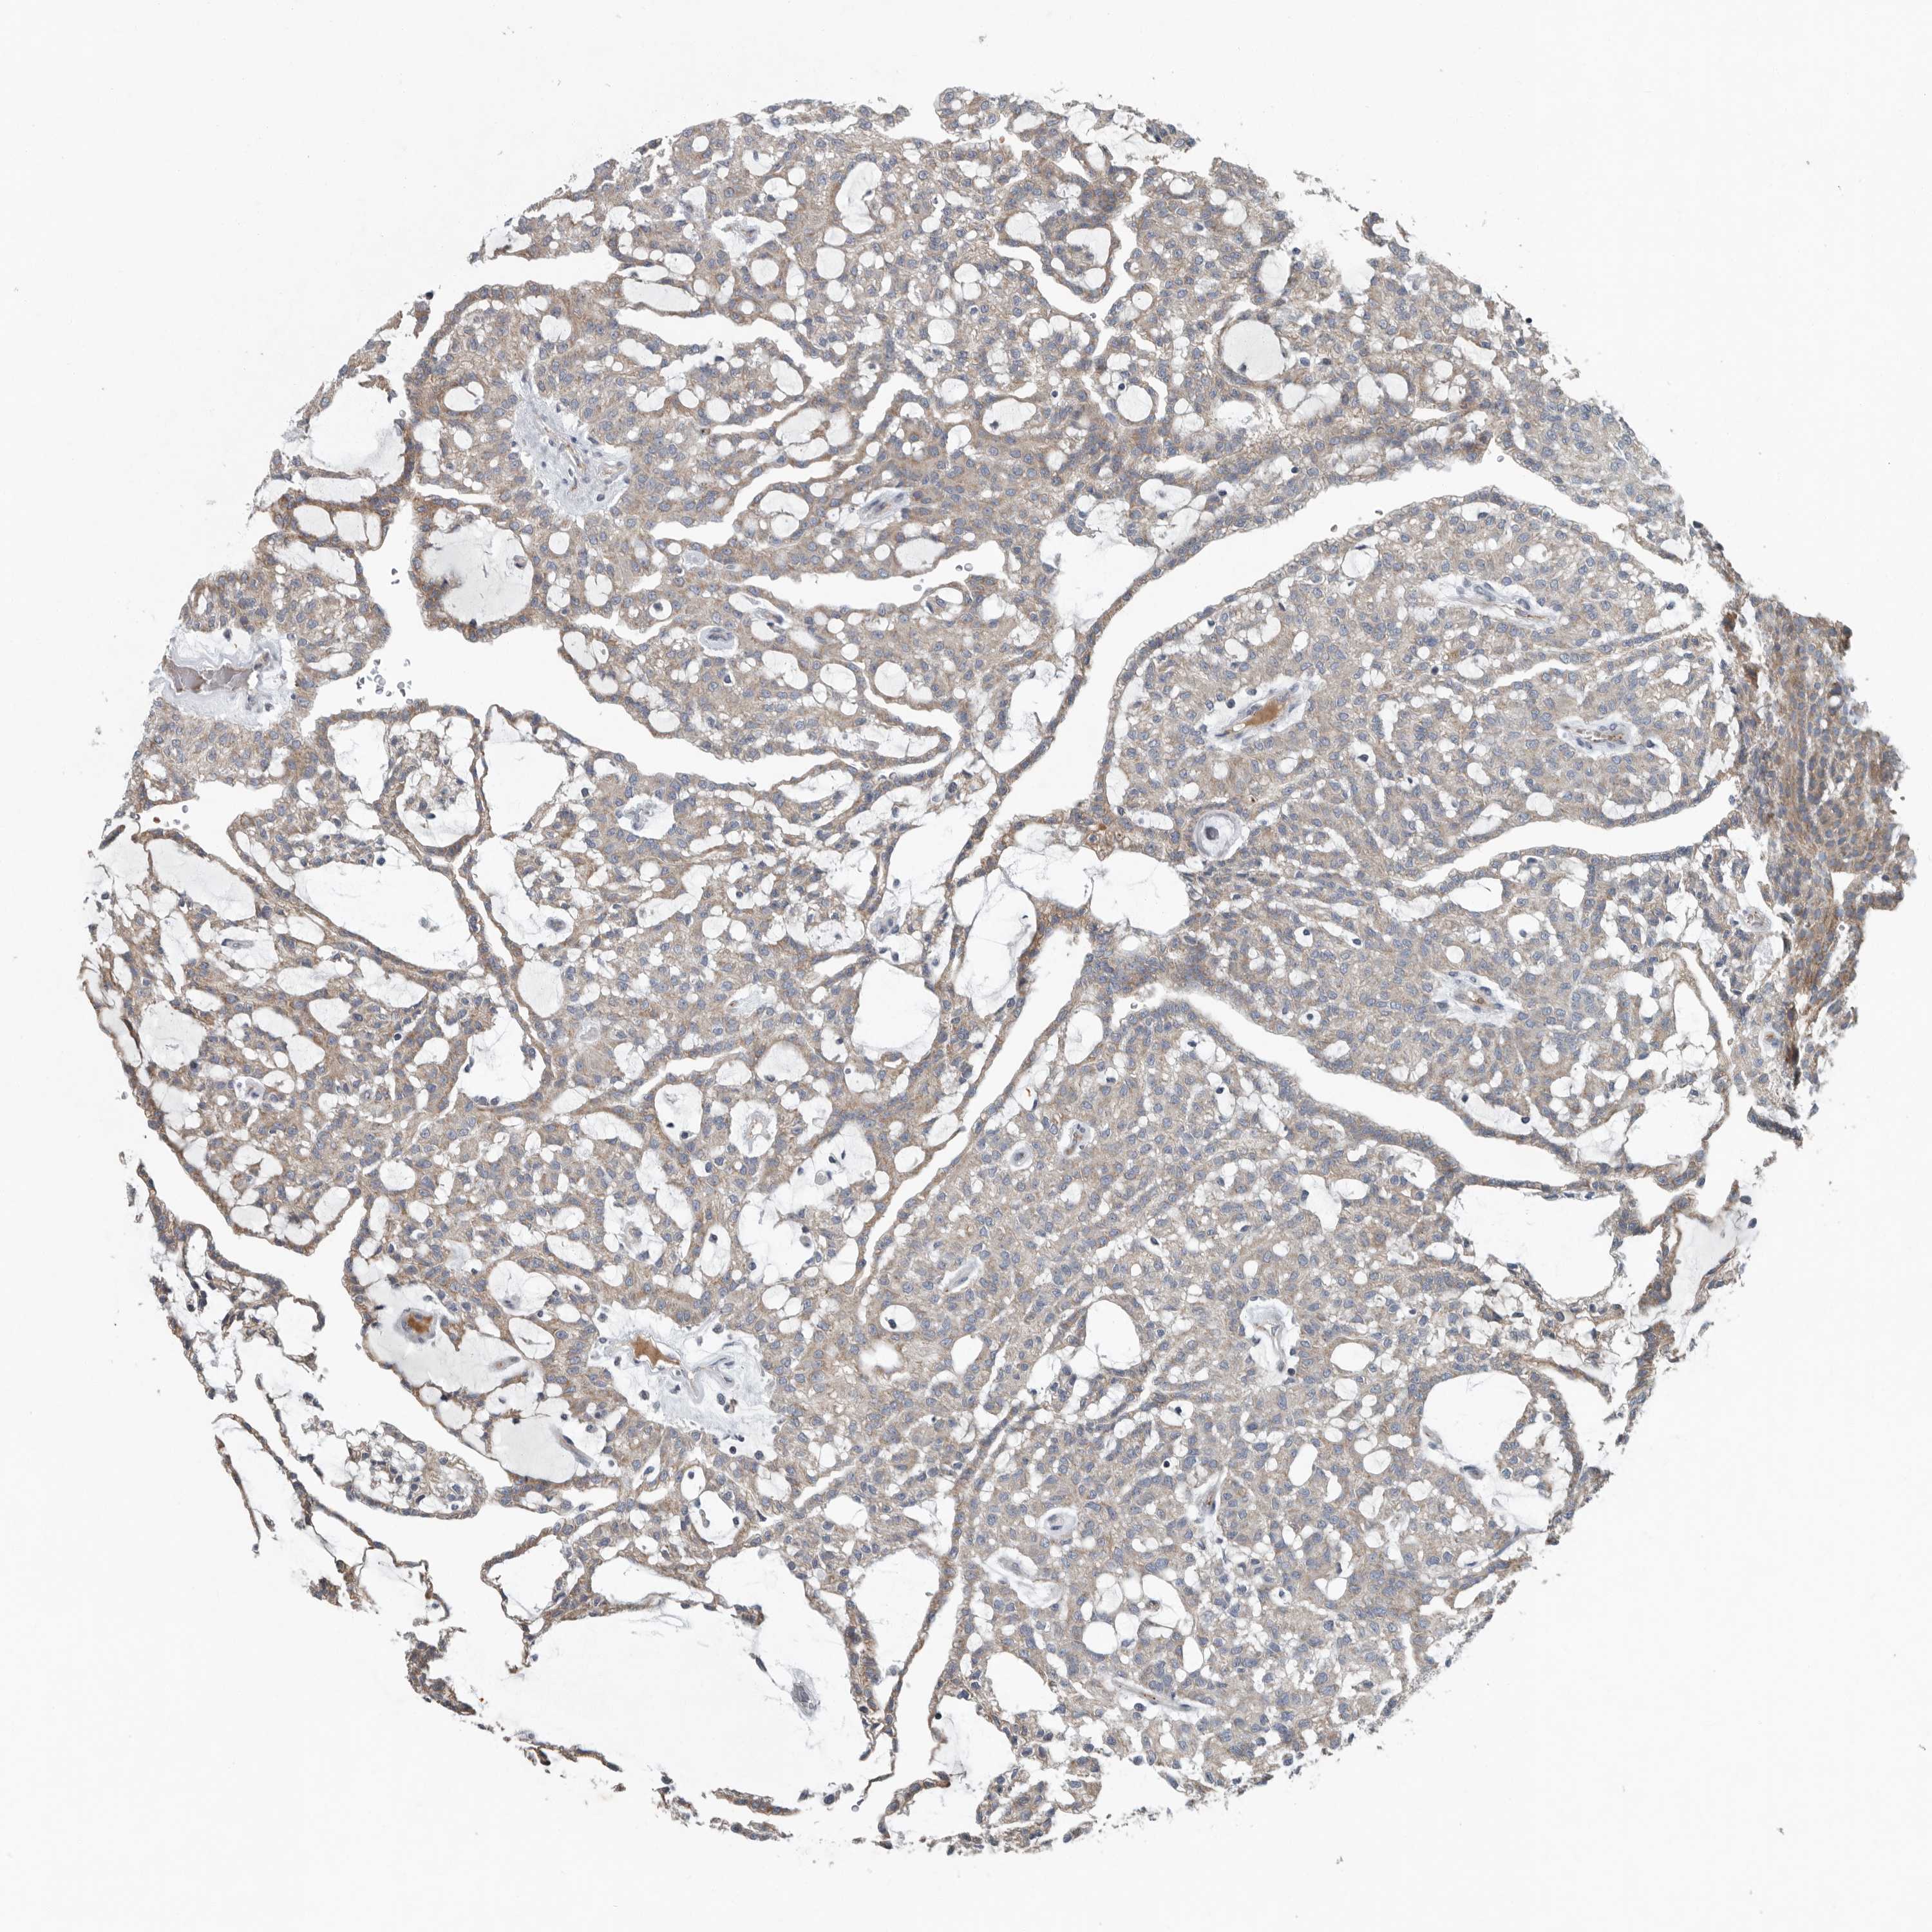

CANCER RENAL CANCER Show tissue menu

KICH TCGA KIRC TCGA KIRC VALIDATION KIRP TCGA PROTEIN RCC CPTAC PROTEIN EXPRESSION